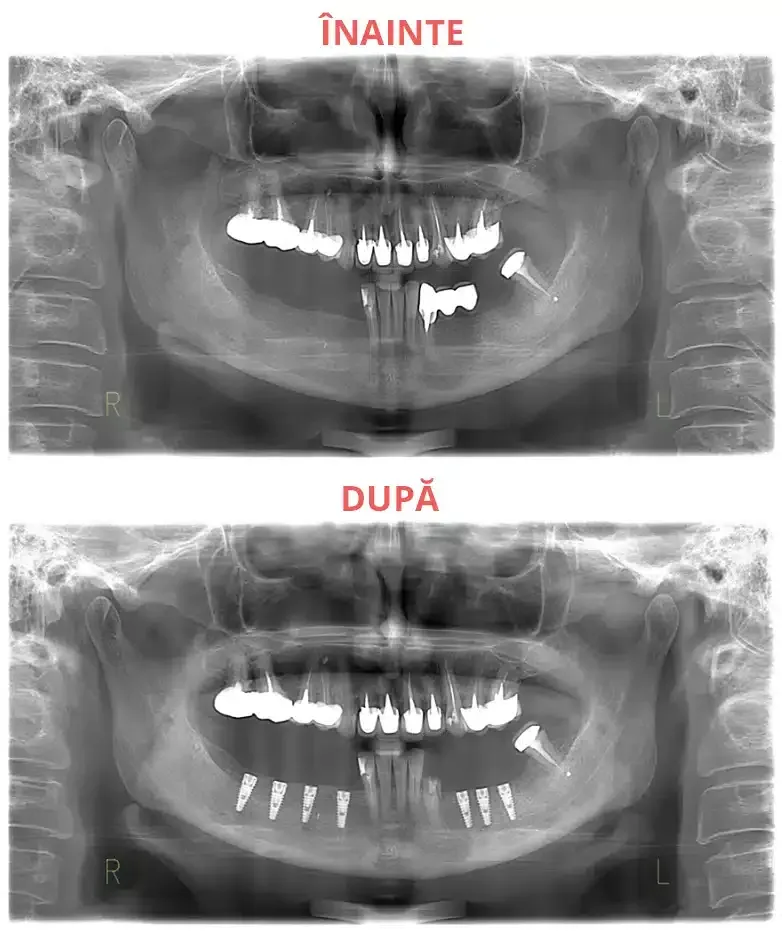

Această procedură implică inserarea unui număr de implanturi dentare (4, 6 sau 8) în cavitatea bucală. Numărul exact de implanturi este determinat de către medicul chirurg, în funcție de evaluarea clinică, de structura osoasă și de cerințele individuale ale pacienților.